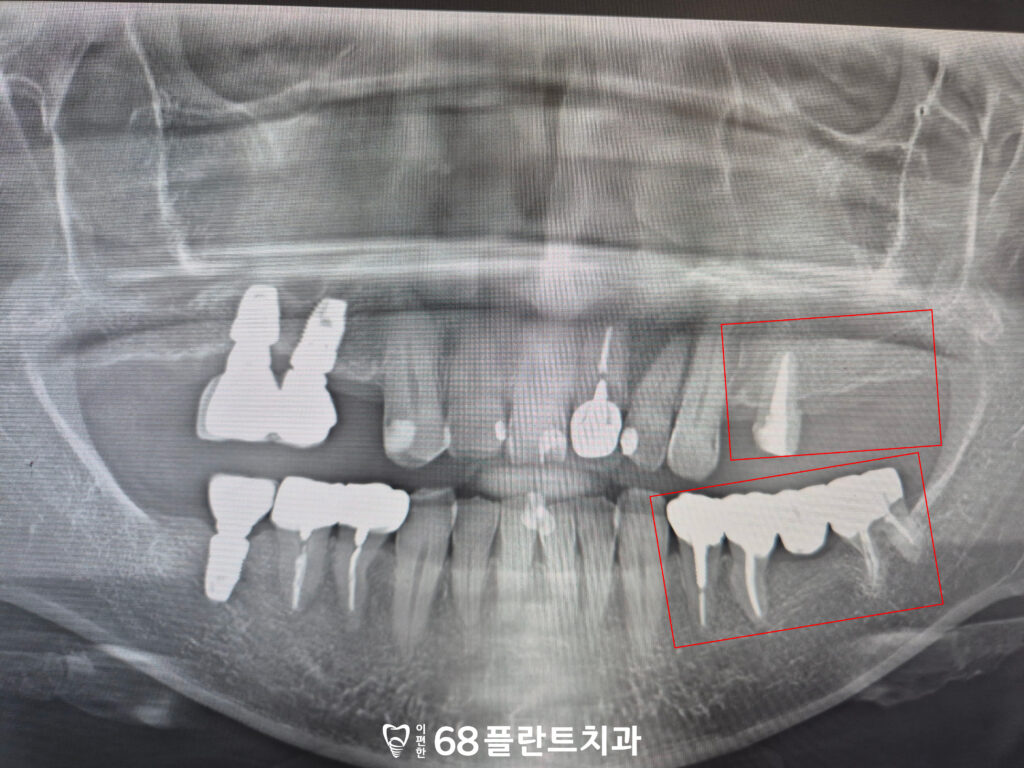

파노라마 촬영을 통해 확인해보니,

왼쪽 위 어금니 부위는

치아가 상실되어 있었고

작은 어금니는 신경치료까지만

진행된 상태였습니다.

또한 왼쪽 아래 브릿지 치아들은

엑스레이상에서는 뚜렷한 문제가

드러나지 않았지만,

환자분께서 식사 시 통증을 호소하셨고

이를 통해 치아에 금이 간 상황임을

확인할 수 있었습니다.